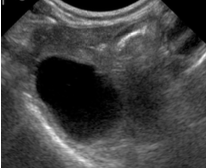

DX? vessie

zone de fibrine intraluminale (inflammation)